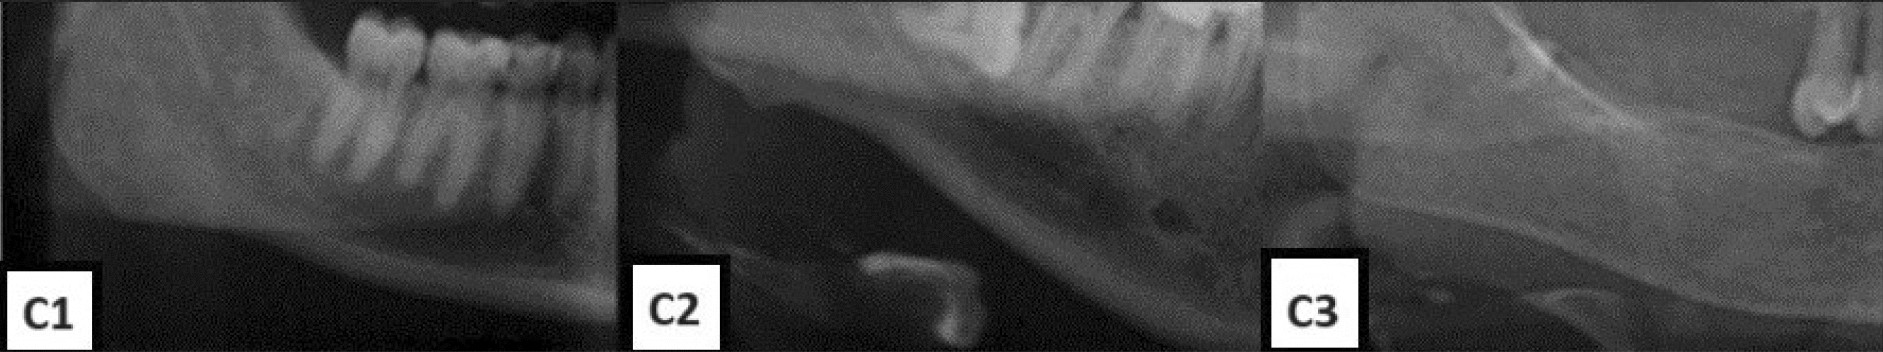

Visible upper cortical line of the left mandibular canal | Download Scientific Diagram